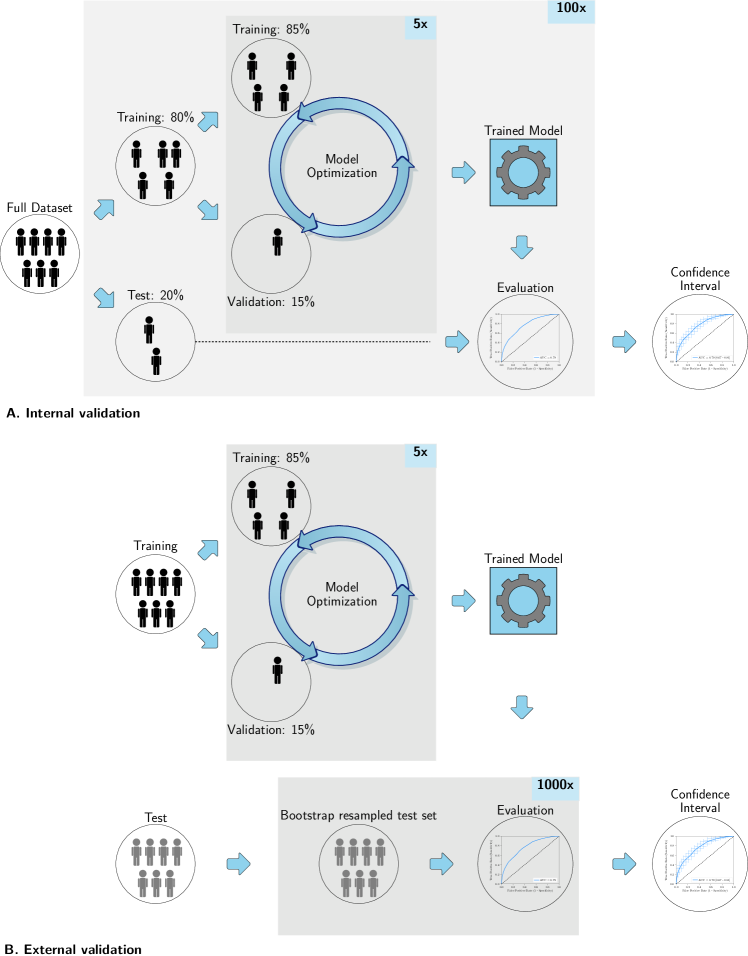

Evaluation using a single dataset is performed through a random-split cross-validation with , see Figure A.1(a) for a schematic overview. A random-split cross-validation was chosen, as it has a relatively low computational complexity while facilitating estimation of the generalization error [65, 54]. In each iteration, the data is randomly split in 80% for training and 20% for testing in a stratified manner. In each random-split iteration, all CASH optimization is performed within the training set according to Algorithm 1 to eliminate any risk of overfitting on the test set. When a fixed, independent training and test set are used, only the second, internal random-split cross-validation with on the training set for the CASH optimization is used, see Figure A.1(b).

Performance metrics used for evaluation of the test set include the Area Under the Curve (AUC), calculated using the Receiver Operating Characteristic (ROC) curve, , sensitivity, specificity, precision, recall, accuracy, and Balanced Classification Rate (BCR) [86]. When a single dataset is used, and thus a random-split cross-validation, 95% confidence intervals of the performance metrics are constructed using the corrected resampled t-test, thereby taking into account that the samples in the cross-validation splits are not statistically independent [54]. When a fixed training and test set are used, 95% confidence intervals are constructed using 1000x bootstrap resampling of the test dataset and the standard method for normal distributions (Efron and Tibshirani [22], table 6, method 1). ROC confidence bands are constructed using fixed-width bands [51].

For each experiment, per patient, one or more scan(s) and segmentation(s), and a ground truth label are provided. All scans were made at “baseline”, i.e., before any form of treatment or surgery. One dataset (the Glioma dataset) consists of a fixed, independent training and test set and is thus evaluated using 1000x bootstrap resampling. In the other eleven datasets, the performance is evaluated using the random-split cross-validation.